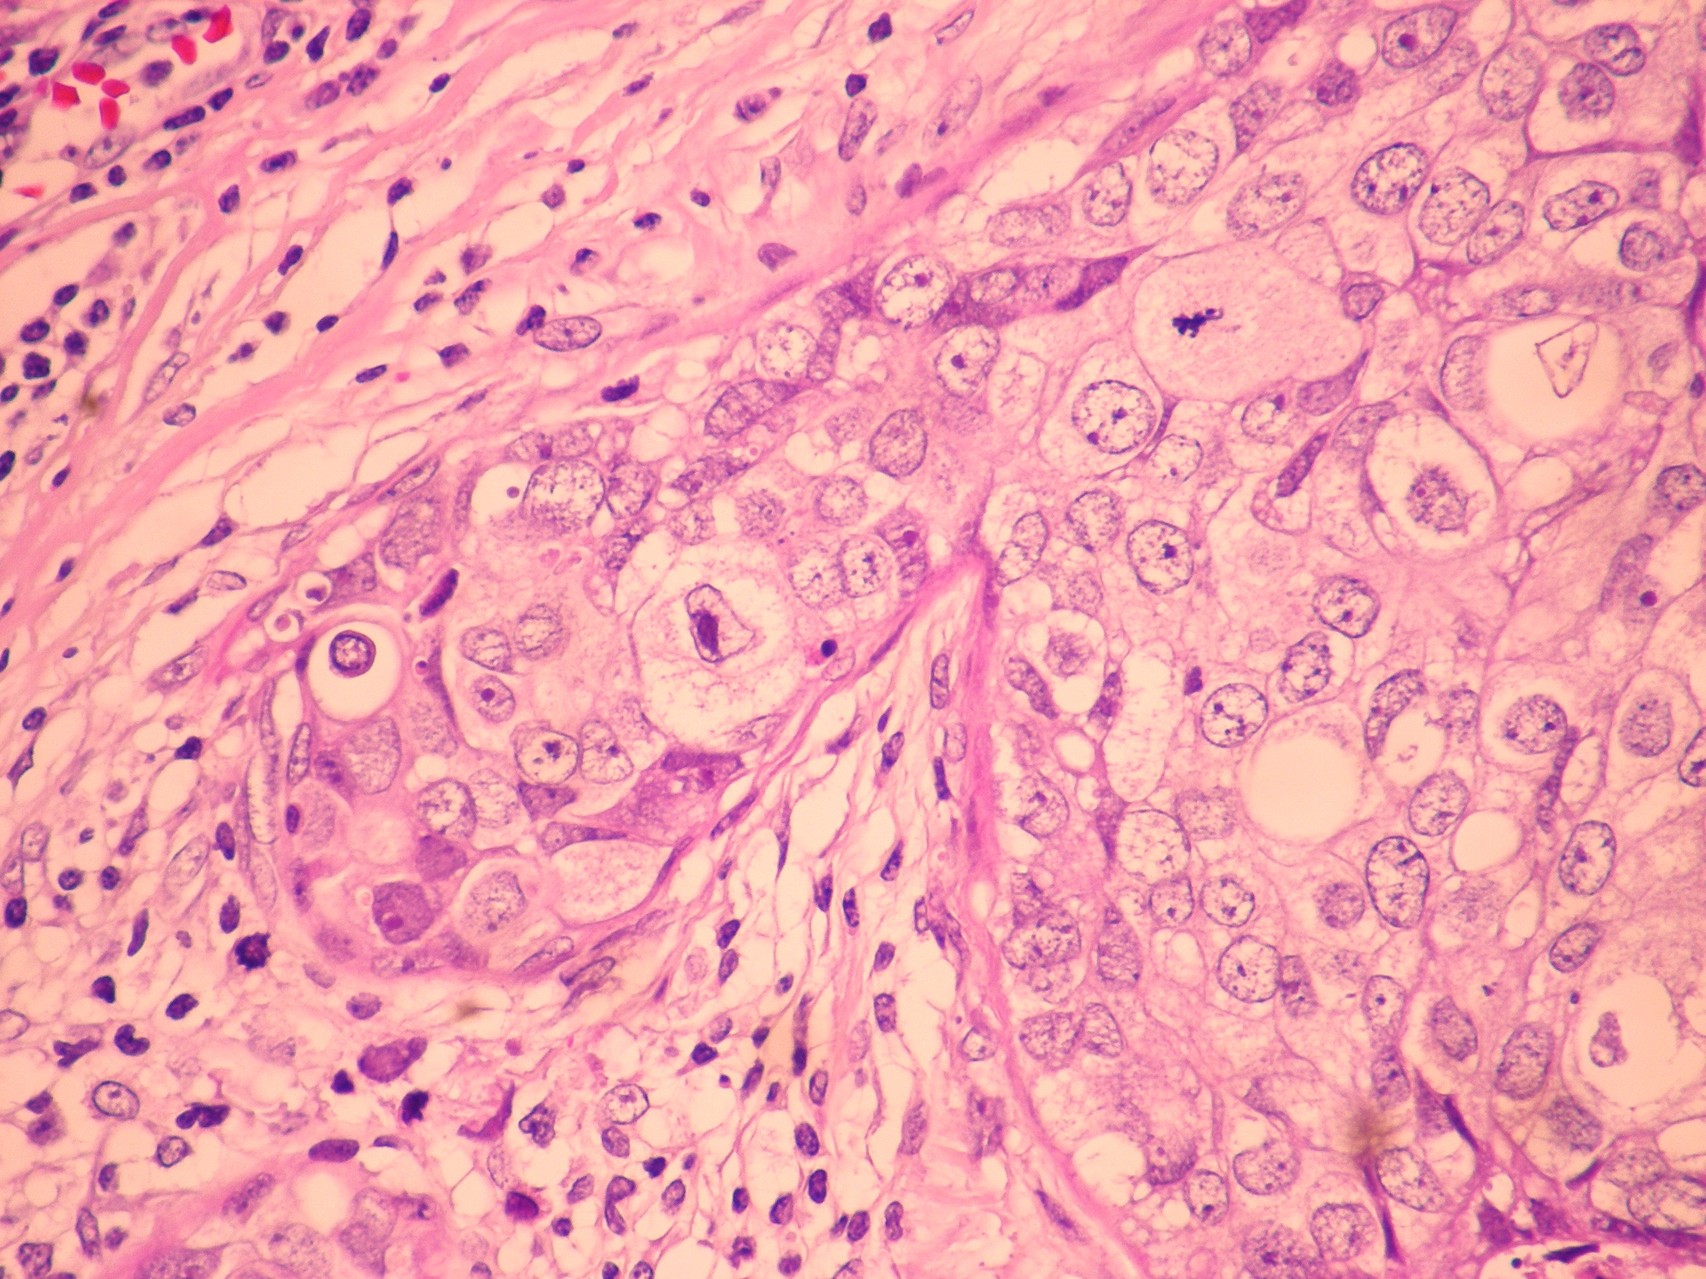

Patología Molecular

El diagnóstico sobre muestras de tejidos y líquidos corporales en plena era de la medicina del futuro, está basado en la integración de técnicas y conocimientos diferentes.

Hoy más que nunca es importante integrar una buena historia clínica con un correcto estudio de imagen y una buena morfología que además puede estar apoyada con proceso especiales complementarios relacionados con la Inmunología, Biología Molecular y Citogenética, generando así un estudio integral conocido como Patología Molecular.